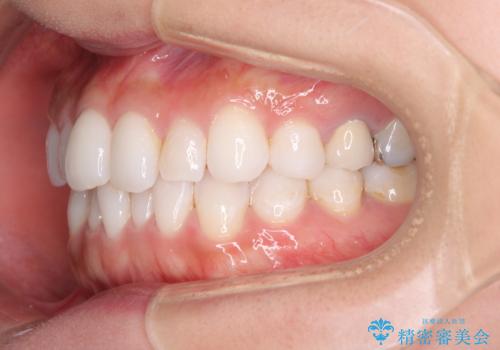

軽度の叢生をインビザライン・ライトで解消

- 前歯が気になるとのことで来院された患者様です。

歯列不正は軽微であったため、インビザライン・ライトにより、費用を抑えて矯正治療を行うこととしました。

短期間で気になる前歯の歯列を改善することができました。